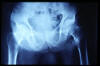

Fractura cuello fémur. Prótesis completa.